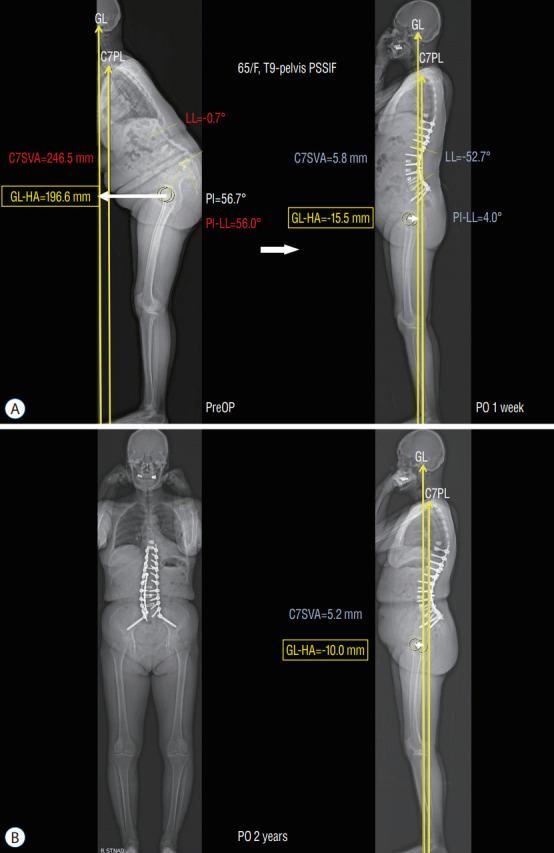

In adult spinal deformity (ASD) surgery, mechanical failure (MF) has been a significant concern for spine surgeons as well as patients. Despite earnest endeavors to prevent MF, the absence of a definitive consensus persists, owing to the intricate interplay of multifarious factors associated with this complication. Previous approaches centered around global spinal alignment have yielded limited success in entirely forestalling MF. These methodologies, albeit valuable, exhibited limitations by neglecting to encompass global balance and compensatory mechanisms within their purview. In response to this concern, an in-depth comprehension of global balance and compensatory mechanisms emerges as imperative. In this discourse, the center of gravity and the gravity line are gaining attention in recent investigations pertaining to global balance. This narrative review aims to provide an overview of the global balance and a comprehensive understanding of related concepts and knowledge. Moreover, it delves into the clinical ramifications of the contemporary optimal correction paradigm to furnish an encompassing understanding of global balance and the current optimal correction strategies within the context of ASD surgery. By doing so, it endeavors to furnish spine surgeons with a guiding compass, enriching their decision-making process as they navigate the intricate terrain of ASD surgical interventions.